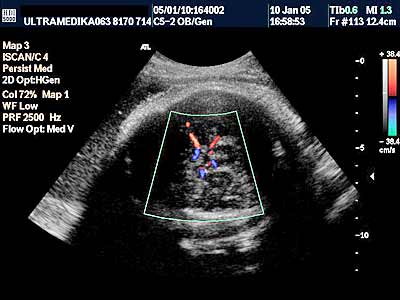

3. Arteriovenske malformacije su ispad prve faze embriogneze tj. histiogeneze. Ona započinje u toku 6-11 nedelje gestacije kada ne dolazi do formiranje moždanih kapilara. Rezultat ovoga je direktna komunikacija između cerebralnih (moždanih) arterija i dubokih drenažnih vena mozga. Ovakva situacija dovodi do direktnog šanta arterijske krvi u vene, naime "zaobilaze“ se neadekvatno formirani kapilari u mozgu. Iako je greška nastala rano, tek sa ukupnim povećanjem volumena mozga i količine krvi koja kroz njega prolazi a koja nastaje u III trimestru, moguće je ultrazvukom registrovati vene koje su postale značajno proširene i aneurizmatske. Jedna od najčešće prisutnih patoloških komunikacija je tok krvi u drenažnu venu Galen-i. Njeno aneurizmatsko proširenje može dovesti do kompresije na mozak koji zaostaje u rastu -postaje hipoplazičan i atrofičan a može doći i do formiranja hidrocefalusa.

A) Savremena dijagnostika korišćenjem Broad band kolor Dopplera (Broad band-CD) i kolor Power Dopplera (CPD) bez obzira na količinu krvi koja prolazi kroz vaskularnu anomaliju i bez obzira pod kojim uglom je moguće poslati ultrazvučni talas, je u stanju da postavi dijagnozu ove ozbiljne vaskularne malformacije CNS. U nepovoljnim uslovima standardna ultrazvučna tehnika sa CD nije u stanju da prikaže ni normalne krvne sudove Wilisovog šestougla niti duboke drenažne vene . Jedino savremena ultrazvučna tehnika je u stanju da postavi dijagnozu bez obzira na položaj ploda koji obično bitno ne menja svoju poziciju u toku pregleda u III trimestru trudnoće. Takođe CPD tehnika je u stanju da proceni tačno hemodinamiku moždane i srčane cirkulacije i da tačnu prognozu. Ovo je važno jer se neke aneurizme vene Galen-i mogu lečiti nakon rađanja deteta embolizacijom krvnih sudova.

U III trimestru je moguće registrovati i druge AV malformacije mozga, koje ranije bez savremene ultrazvučne dijagnostike nisu bile moguće. Posebno treba naglasiti da jedino savremeni aparati sa Broad band CD i CPD i CPA mogu prikazati kompletnu vensku cirkulaciju sinusa neposredno ispod lobanje mozga. Takođe kodiranjem toka arterija mozga moguće je postaviti dijagnozu složene razvojne anomalije mozga (holoprozencefalije). Moramo reći da deca sa ovakvim anomalijama ne bi trebalo da budu rođena.